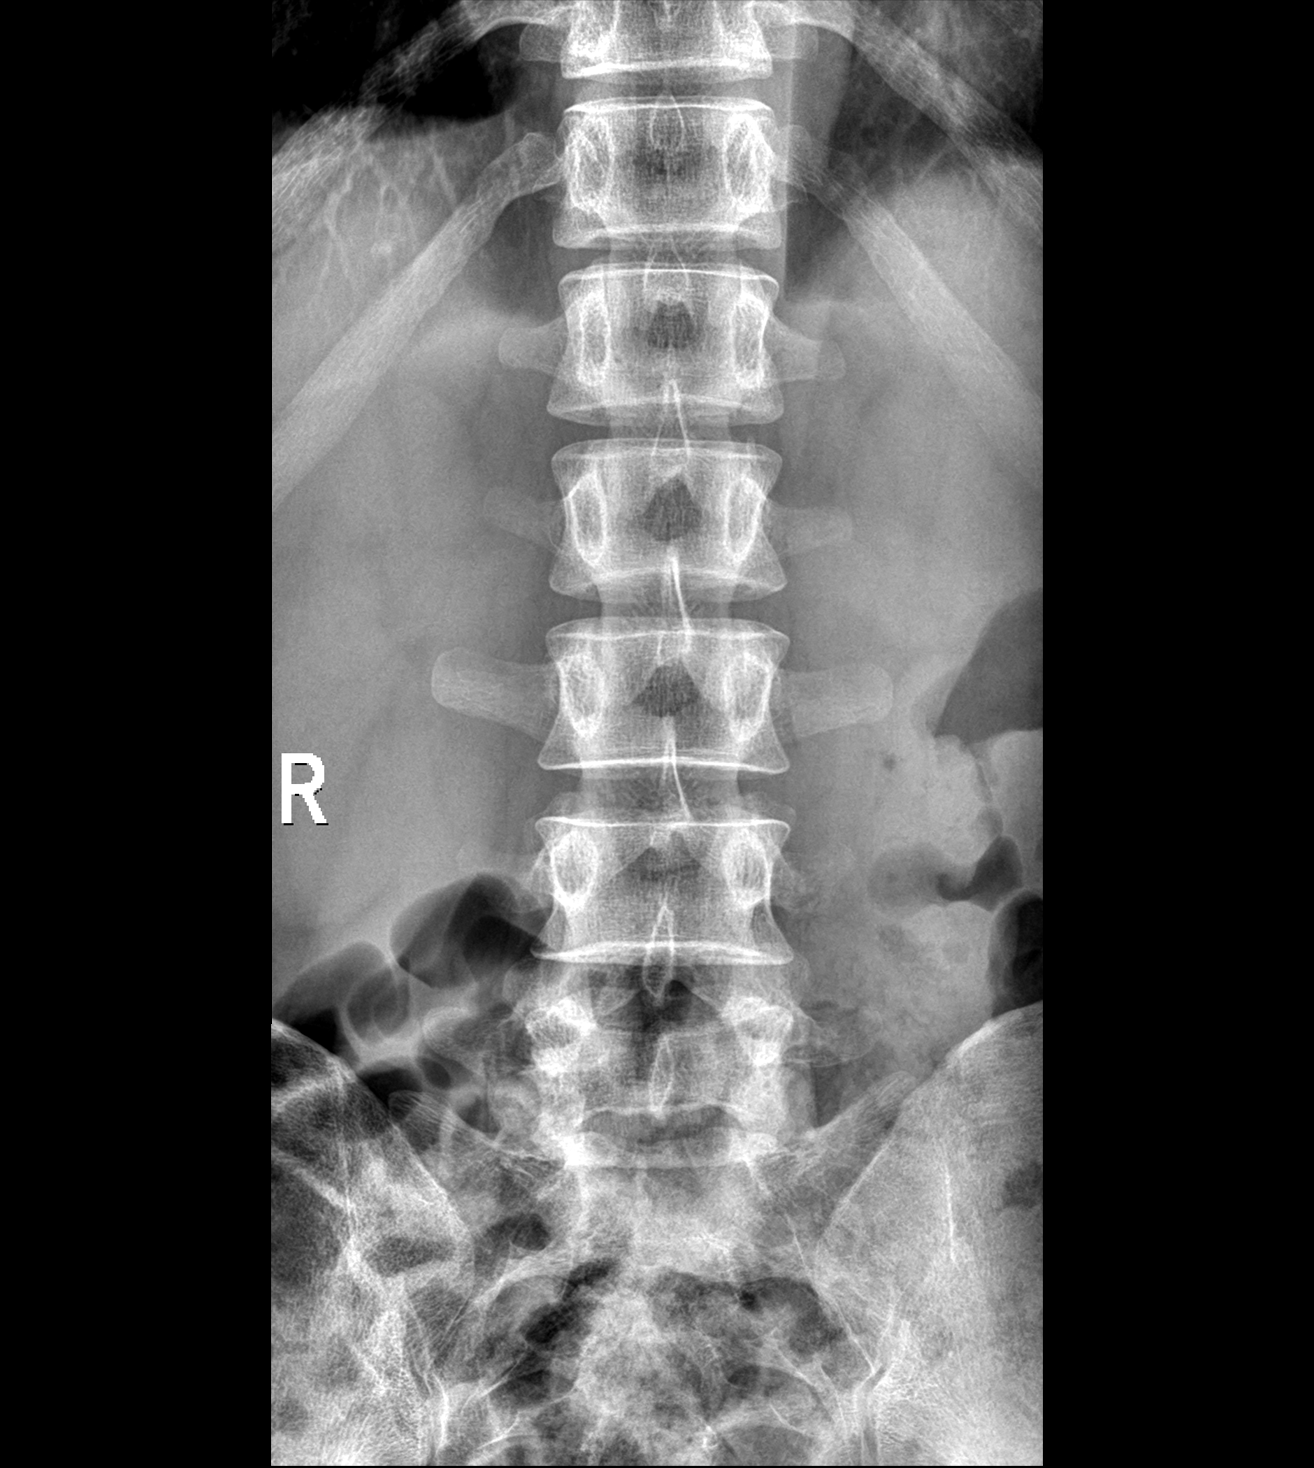

多功能诊断专用动态DR

太阳成集团tyc122cc入口科技全新设计的第四代床式动态DR,集拍片、透视、造影、全身拼接、尘肺体检于一体,一机多能,真正意义上实现全科室应用,提升医院实际效益。

高清动态平板探测器

搭载自主研发超清大视野动态平板探测器,600微米碘化铯大幅提升X线转化效率,独特的非晶硅阵列与高速读取集成电路紧密协作,轻松实现多帧率透视与高清点片。

专业的影像处理系统

“腾灵”系列搭载的IEAE影像处理系统,具备多项发明专利。本系统采用多频域图像处理技术,其6大核心处理模块使影像具有优秀的一致性、柔和性、空间层次感和纹理细腻度,为用户精准诊断病灶奠定了坚实的基础。